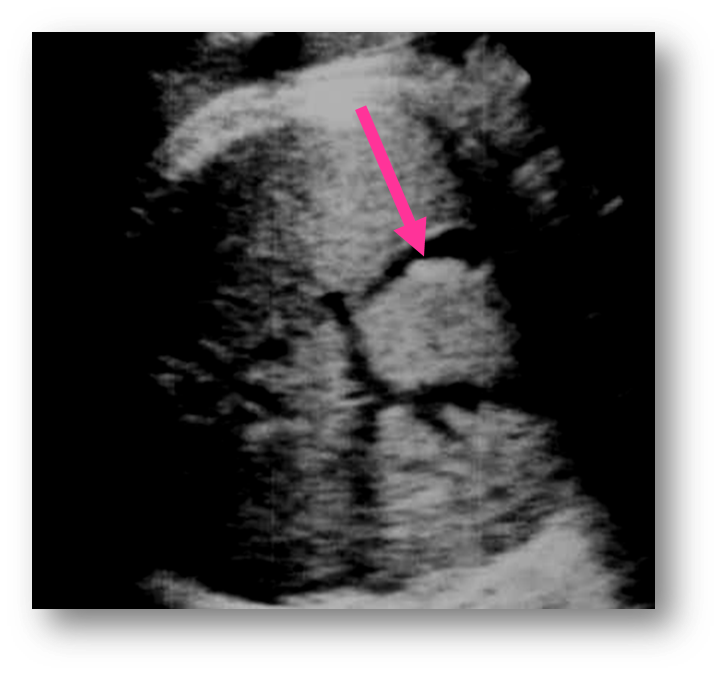

What view is this?

5 chamber view (used to recored aortic root, outflow, LVOT)